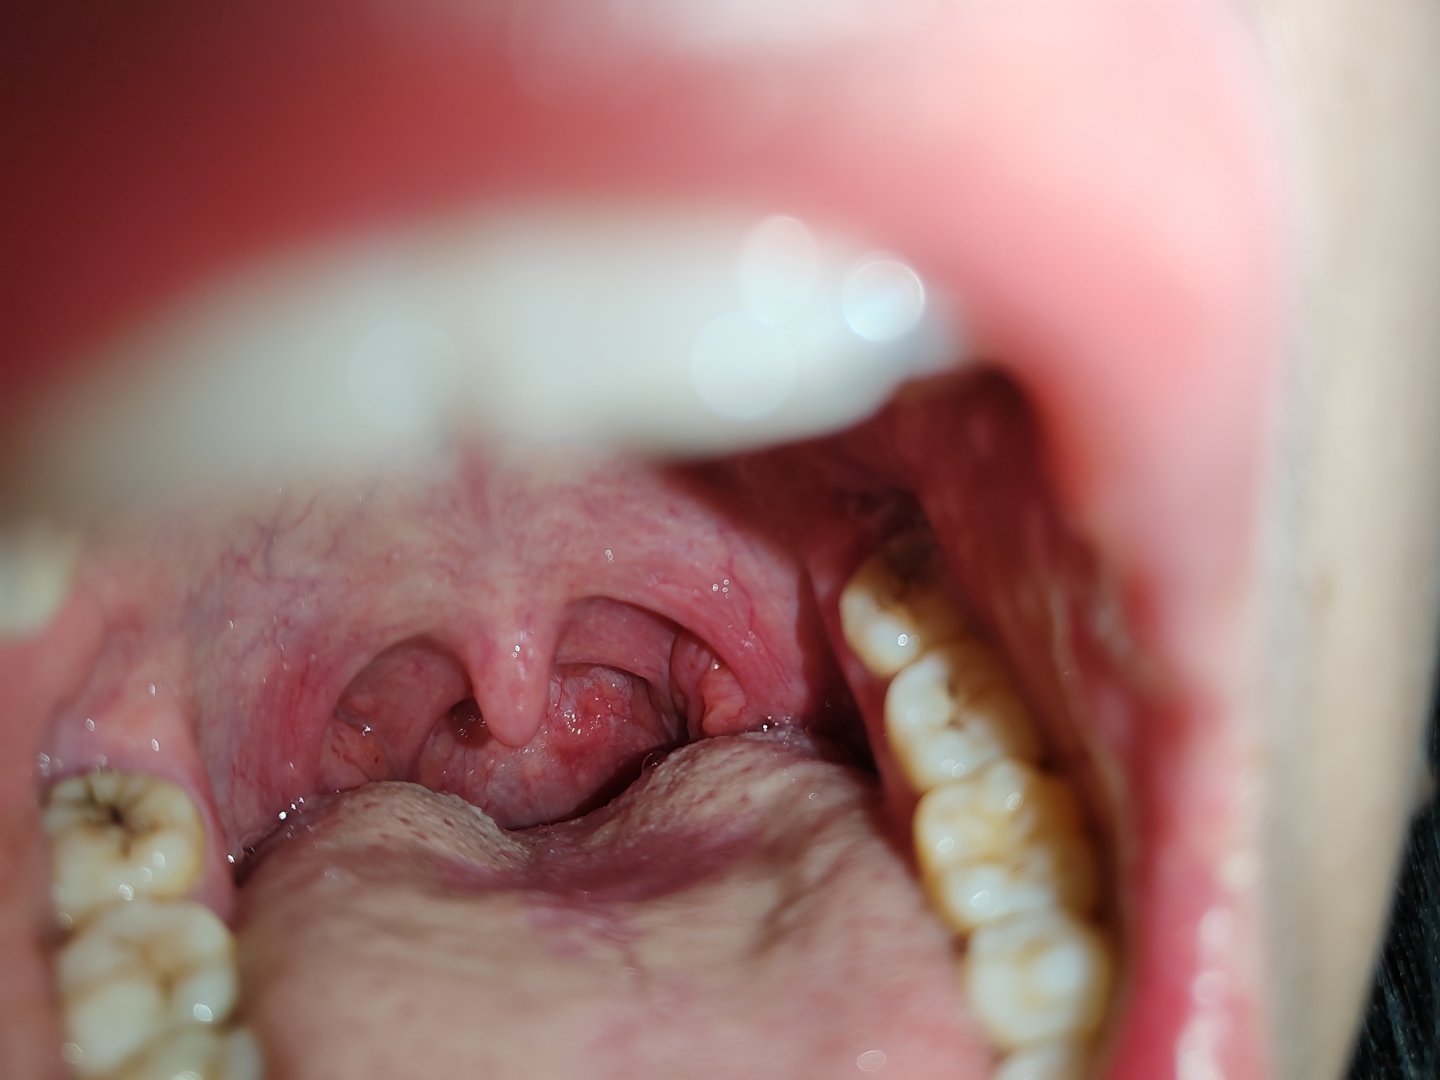

舌根部淋巴滤泡增生,粘膜充血,会厌抬举可,左侧声带我太难受了咽后壁

图片尺寸400x400